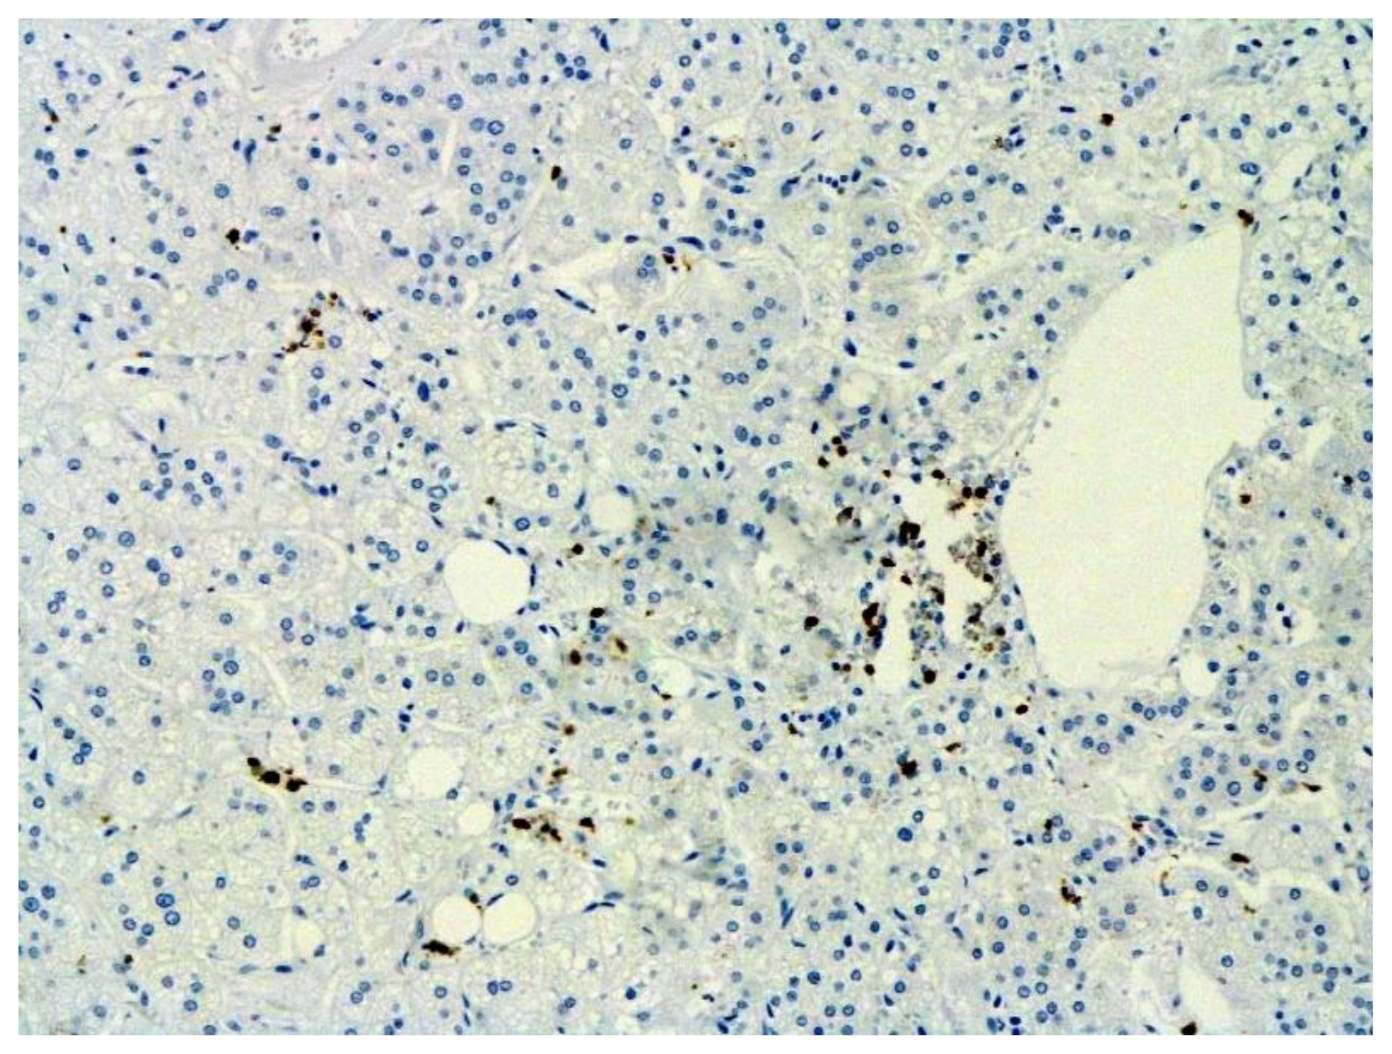

The hallmarks of apoptosis (according to expression of caspase-3) were revealed in the lungs, lymph nodules, and other organs, predominantly in the area with the small granular rhexis (Figure 4 and Figure 5.) The possibility of developing a generalized infection with damage to other organs is evident. Alterative and necrotic changes were seen in parenchymal cells. Sometimes we noted their changes in the nuclei of the cells in the lymph nodes, intestines, soft meninges, heart, pancreas, kidneys, and spleen. We succeeded in detecting spike and nuclear antigen of the virus in the lymph nodes (Figure 6), pancreas, brain (Figure 7), and adrenals. We described certain lesions in the adrenals that are probably associated with the SARS-CoV-2 virus [25].

Figure 6. Nuclear antigen of SARS-CoV-2 (arrow) in lymph node. IHC ×400.